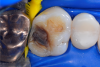

Fig 2. Image of the tooth before the restoration.

Figure 2

In this case, a female patient presented with an asymptomatic tooth that had an incomplete fracture on the distal palatal cusp and potentially the distal buccal cusp.1 The patient was highly motivated to avoid extensive dentistry and had "dead jaw syndrome" from a history of using bisphosphonate medication (Figure 1 through Figure 4). The solution was to perform a composite overlay on the tooth.